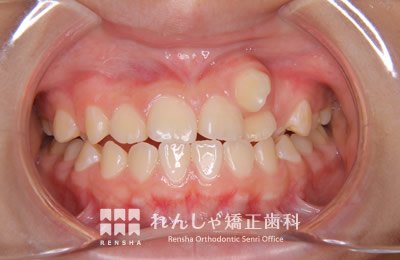

中高生

永久歯列はほぼ完成してしますが、歯列を側方だけでなく後方へも拡大し、埋まっていた右上奥歯を引っ張り出しています。

| 主訴 | 埋まったままでてこない歯がある |

|---|---|

| 診断名 | Angle Class II 小臼歯の埋伏と叢生を伴う上顎前突 |

| 初診時年齢 | 13歳5か月 |

| 装置名 | マルチブラケット装置 |

| 抜歯非抜歯 | 非抜歯 |

| 治療期間 | 2年3か月 |

| 費用の目安 | 約82万円+消費税(検査料金、都度の処置費用等も合わせた総額) |

| リスク副作用 | 歯の移動に伴う軽微な歯根吸収、歯槽骨吸収、歯肉退縮(本症例では軽度の歯根吸収を認めた)、矯正器具装着中のカリエスリスク増大(本症例ではカリエス発生無し) |